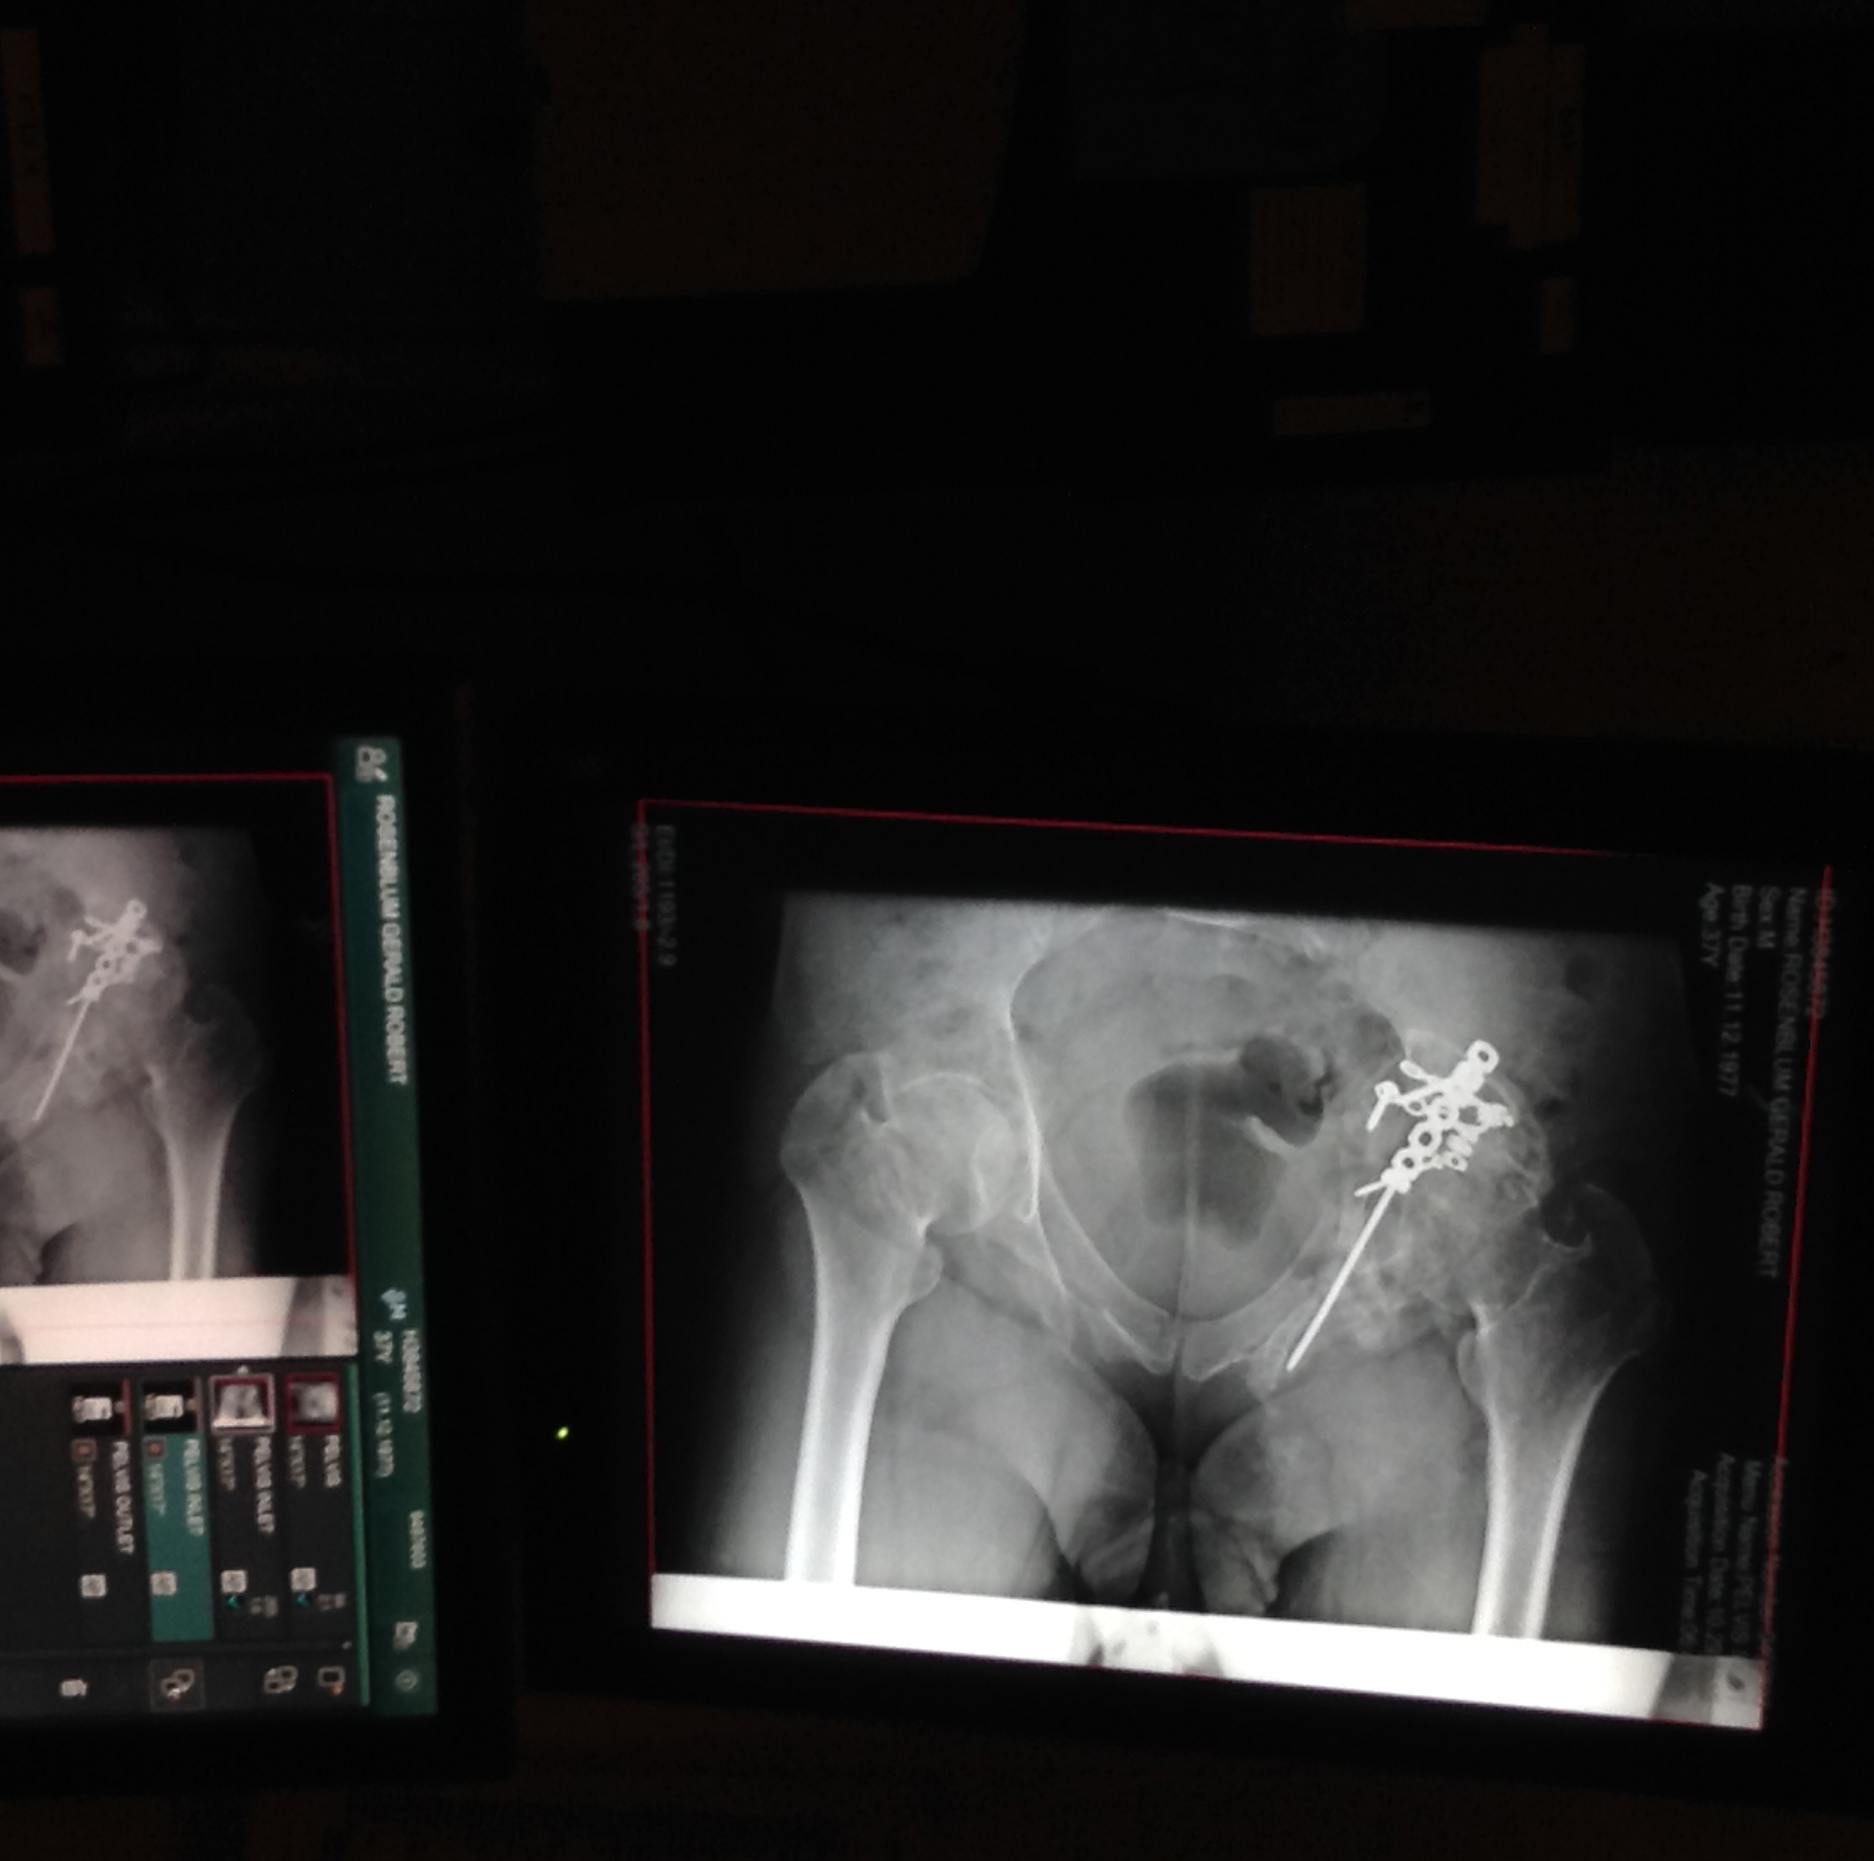

SWORD IN THE STONE